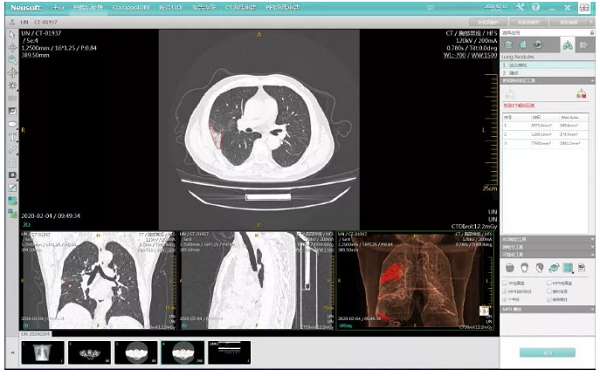

疫情进入攻坚战的重要时刻,快速有效地筛查疑似病例是当前战疫的重点。依托东软医疗与广州医科大学附属第一医院所属广州呼吸健康研究院(钟南山院士团队)共同组建的“国家呼吸系统疾病临床医学研究中心呼吸影像大数据与人工智能应用联合实验室”,联合吉林大学第一医院、武汉市第一医院等多家奋战在抗疫一线的医疗机构,东软医疗快速研发和推出了新冠肺炎智能辅助筛查系统——“火眼AI”。

“火眼AI”是根据最新的新冠肺炎影像学诊断指南和专家共识,通过深入分析新冠肺炎的影像学征象,集新冠肺炎早期筛查、病灶快速检测、疗效评估和病情进展分析的综合解决方案。东软医疗智能医学影像云平台NeuMiva搭载的“火眼AI”系统,在疫情期间向全国的医疗机构免费开放使用。

“火眼AI”利用人工智能技术,可快速针对患者CT影像进行新冠肺炎相关的典型征象的智能检测,可快速标记病灶位置、精准评估病灶情况。并通过本地版及云端版等多种应用形态的方式实现快速部署,医院可根据实际需求选择对应的应用形态。